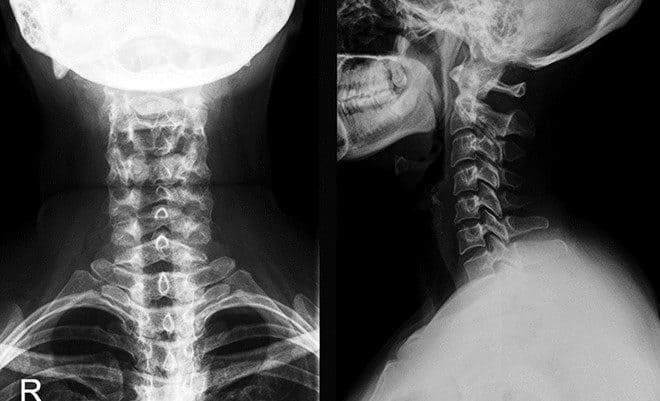

Функциональные снимки шейного отдела позвоночника (со снимком)

Функциональный рентген шейного отдела позвоночника предназначен для выявления поражения позвонков различной природы.

Процедура подразумевает проведение функциональных проб. Они помогают оценить подвижность шейного отдела.